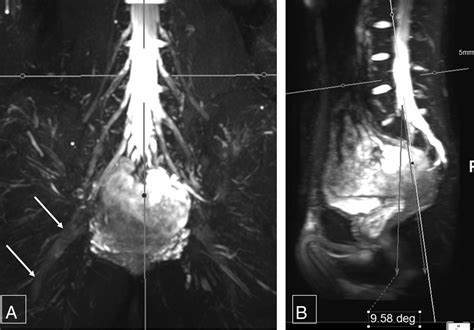

• Nerve Tumors: Detecting and characterizing nerve sheath tumors, such as schwannomas or neurofibromas.

Once the images are acquired, they are analyzed by a radiologist with specialized expertise in musculoskeletal or neuroradiology. The goal is to identify changes in the nerve's appearance. For instance, a healthy nerve typically appears as a thin, uniform structure with a consistent signal. In contrast, an injured or compressed nerve may exhibit:

• Discontinuity or disruption: Clearly visible in cases of severe trauma or nerve rupture.

• Masses or Lesions: Clear identification of tumor growth within or adjacent to the nerve sheath.